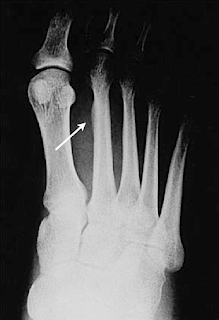

Una persona con una fractura por estrés podría notar lo siguiente. Fractura de estrés 2º metatarsiano Observa el intento de reparación creado alrededor del hueso estresado y fracturado 2º metatarsiano del pie Es la fractura de estrés más conocida y frecuente El metatarsiano es un hueso del pie (El equivalente al metacarpiano de la mano). Descrita por primera vez por el médico de Prusia Breithaupt en 1855, la fractura por estrés es muy común en los reclutas militares y atletas La lesión generalmente afecta a las extremidades inferiores, pero también puede aparecer en las costillas y las extremidades superiores Los lugares más comunes para esta lesión son las tibia, el peroné, metatarsos.

Fractura de estrés 2º metatarsiano Observa el intento de reparación creado alrededor del hueso estresado y fracturado 2º metatarsiano del pie Es la fractura de estrés más conocida y frecuente El metatarsiano es un hueso del pie (El equivalente al metacarpiano de la mano).